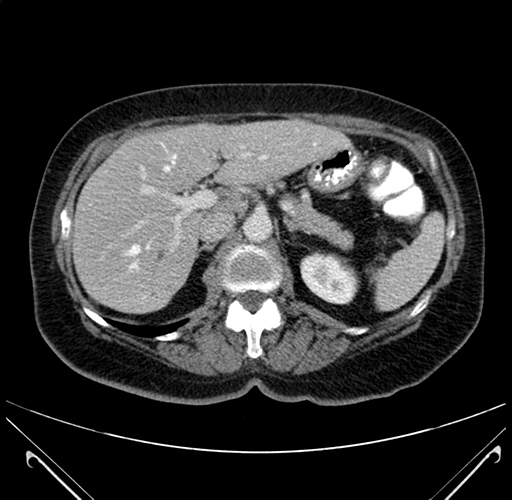

Pre-Chemo: Axial Venous